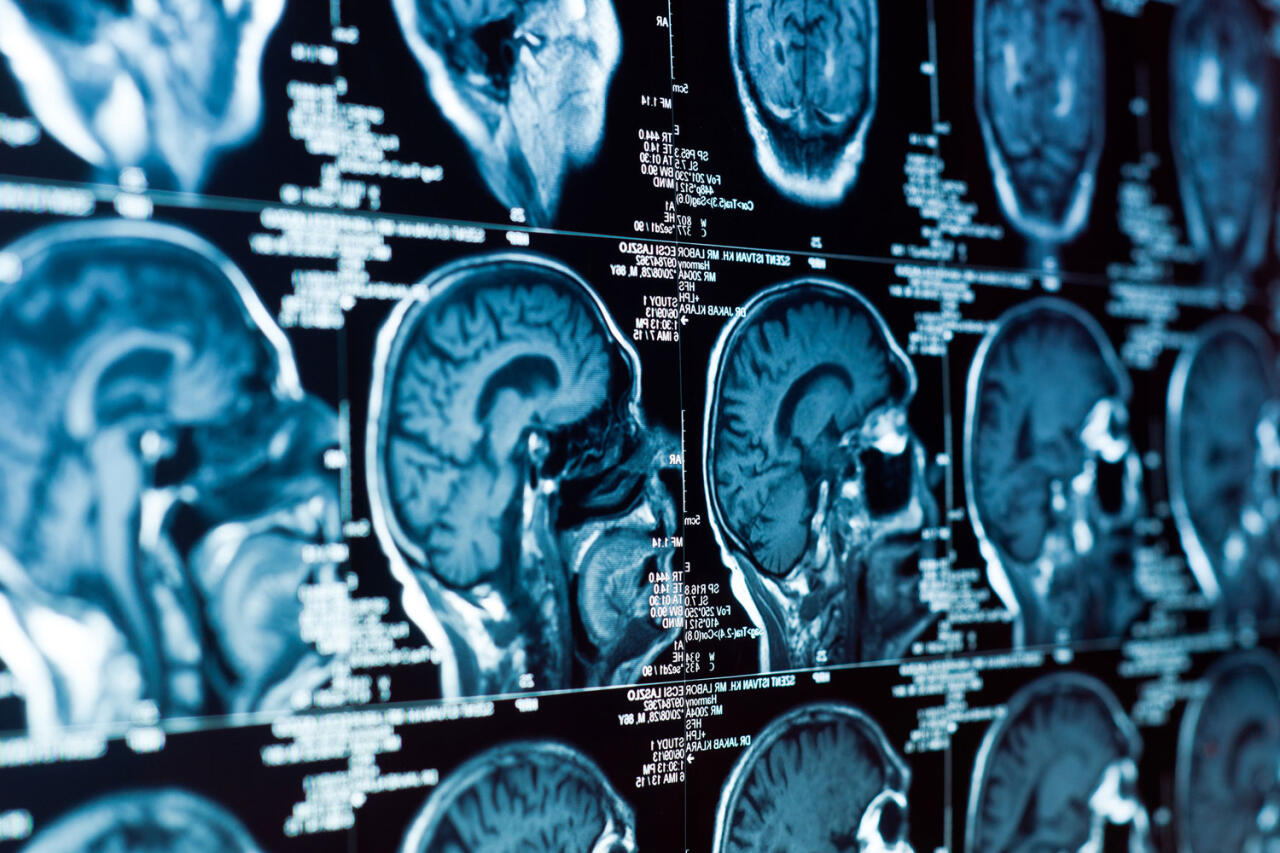

Ученые создали «мини-капсулы» с живыми клеткам для защиты от воспаления мозга

Ученые Хьюстонского методистского центра и Университета Райса создали миниатюрные гидрогелевые капсулы с живыми клетками мозга для подавления нейровоспаления - ключевого механизма, связанного с болезнями Альцгеймера и Паркинсона. Результаты исследования опубликованы в журнале Biomaterials, передает Day.Az со ссылкой на Gazeta.ru.